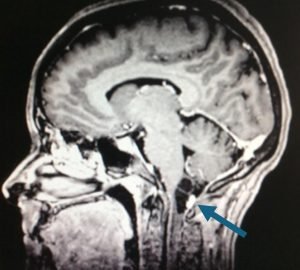

Prueba de elección para tumores de columna y médula espinal. Evalúa partes blandas, relación con la médula y raíces, y detecta compresión, edema, necrosis o hemorragia intratumoral.